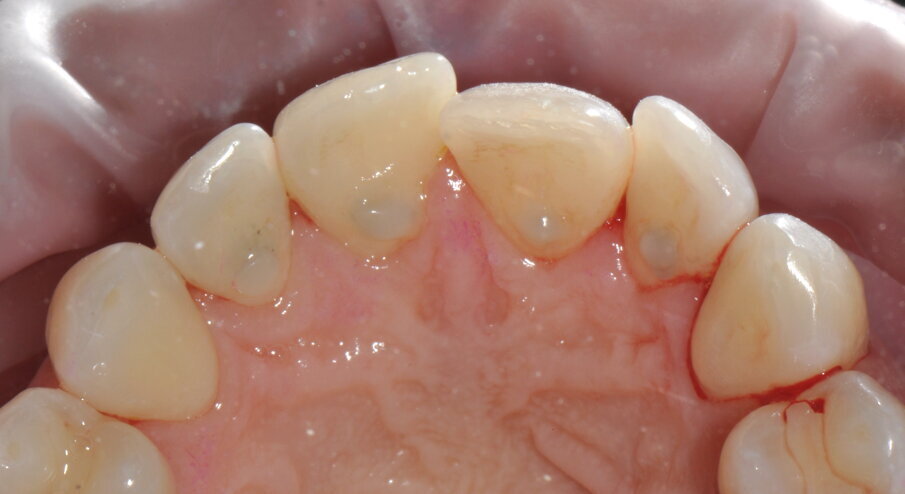

Figg. 5a-5c - Rivalutazione a 2 settimane si noti la completa risoluzione dell’infiammazione gengivale, nelle visioni vestibolare (5a), palatale (5b) e linguale (5c).